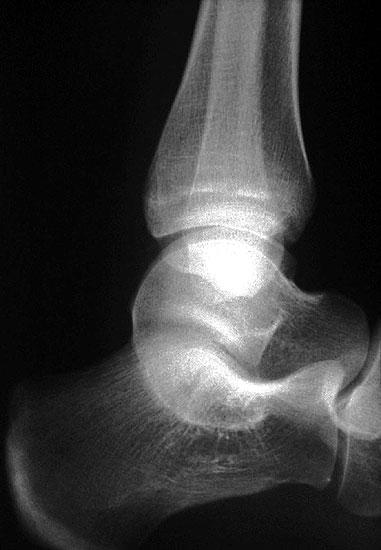

MRT und CT konkurrieren in der Fein-Darstellung der Knochenbrücke, der Beurteilung der nichtbetroffenen Anteile des Subtalargelenkes und der Sekundärveränderungen. Das MRT bietet den Vorzug, bindegewebige und knorpelige Strukturen (Abb. 2) und bei Einsatz von Kontrastmittel auch knöcherne Aktivierungsphänomene genau abzubilden; die knöcherne Feinstruktur und genaue Ausdehnung dagegen ist mit dem Dünnschicht-CT wesentlich exakter darstellbar (Abb.3). In manchen Fällen ist eine 3-D-Rekonstruktion des CT hilfreich. Besonders wichtig ist eine geeignete Schichtebenen-Wahl:

Die zweite wichtige Form tarsaler Coalitiones findet sich im medialen Bereich des Subtalargelenkes, am häufigsten unter Einbeziehung der medialen, mittleren Facette des talocalcanearen Gelenkes (Abb. 9). Die Ausdehnung der zunächst fibrösen, später zunehmend verknöcherten Brückenbildung kann sehr unterschiedlich Anteile der hinteren Kammer des unteren Sprunggelenkes mitumfassen; auch rein dorsomediale Formen ohne Einbeziehung der medialen Facette werden beobachtet (Abb. 2) 67 (Hamel 2008).

Diagnostisch sollte neben Röntgenübersichtsaufnahmen (indirekte radiologische Zeichen: Dorsaler Traktions-Osteophyt am Taluskopf, „talar beaking“; kontinuierliche Linie der Trochlea-tali-Kontur übergehend in die Sustentaculum-tali-Kontur, „C-Zeichen“ (Abb. 11) 10) immer die dreidimensionale Bildgebung eingesetzt werden. Das MRT (mit Kontrastmittel) kann die Struktur der Brückenbildung und z.B. die Qualität des Restgelenkes (Knorpel-Dicke) besonders gut abbilden; das Dünnschicht-CT zeigt die knöcherne Feinstruktur im Bereich der Coalitio und den oft sehr schrägen Spalt-Verlauf im Frontalschnitt dagegen häufig genauer. Meist findet sich die Überbrückung im Bereich der medialen Facette; die Schichten sollten jedoch bis weit nach dorsal beurteilt werden, da ansonsten dorsomediale Formen übersehen werden können. Rozansky et al 7 unterschieden fünf morphologische Typen auf der Basis von 3-D-CT-Rekonstruktionen. Allerdings ist eine prognostische Zuordnung bisher nicht möglich.